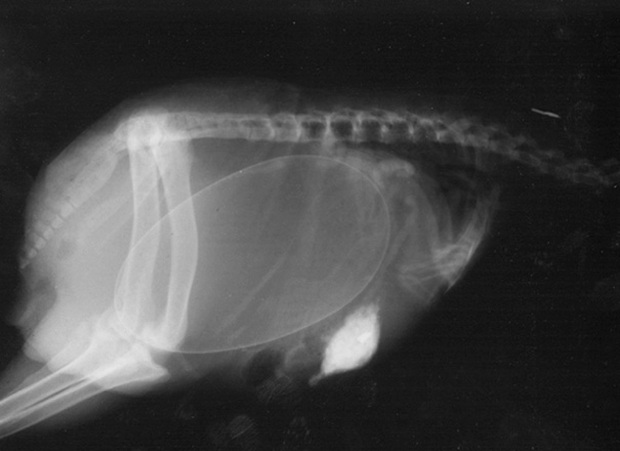

Một mẹ chim Kiwi đang mang trong mình quả trứng khá lớn so với kích thước bụng của nó. Chim Kiwi là loài chim không bay bản địa New Zealand. Trong họ nhà chim, trứng của Kiwi có kích thước lớn nhất khi so với kích thước cơ thể.

Cận cảnh hình chụp X-quang một cô mèo đang mang thai và loạt ảnh động vật mang bầu khiến người xem rùng mình nhưng rồi thấy đẹp khó tả - Ảnh 5.